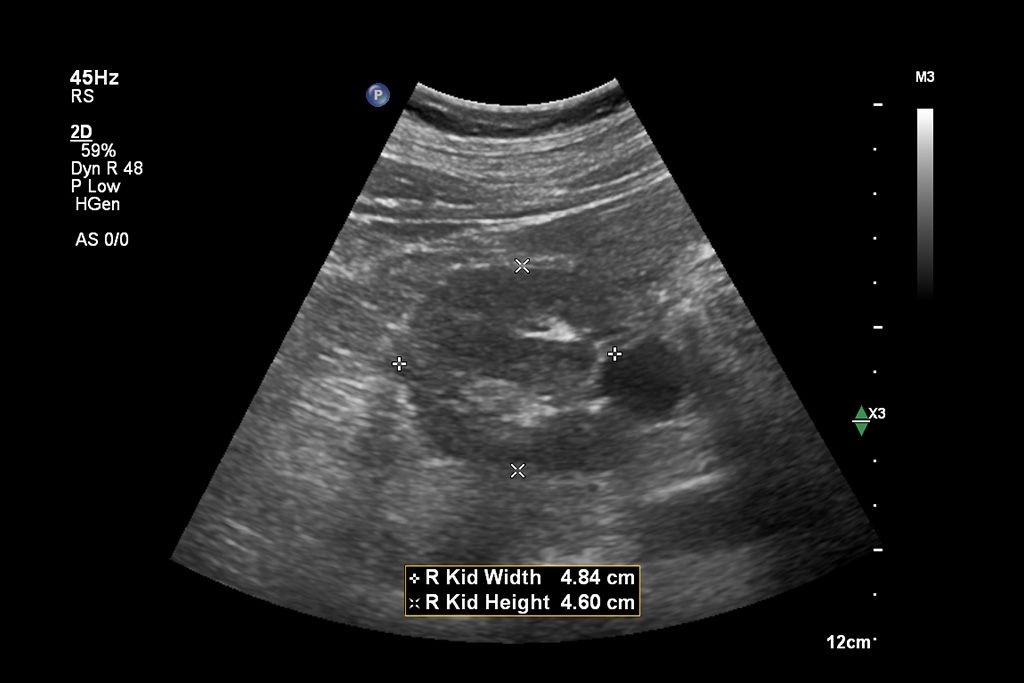

AI-driven Auto Measure Abdomen - Philips